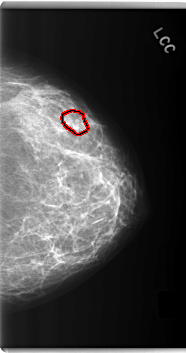

C_0277_1.LEFT_CC

LEFT_CC LINES 6000 PIXELS_PER_LINE 3152 BITS_PER_PIXEL 12 RESOLUTION 50 OVERLAY

FILE: C_0277_1.LEFT_CC.OVERLAY

TOTAL_ABNORMALITIES 1

ABNORMALITY 1

LESION_TYPE MASS SHAPE LOBULATED MARGINS CIRCUMSCRIBED

ASSESSMENT 3

SUBTLETY 4

PATHOLOGY BENIGN

TOTAL_OUTLINES 1

BOUNDARY